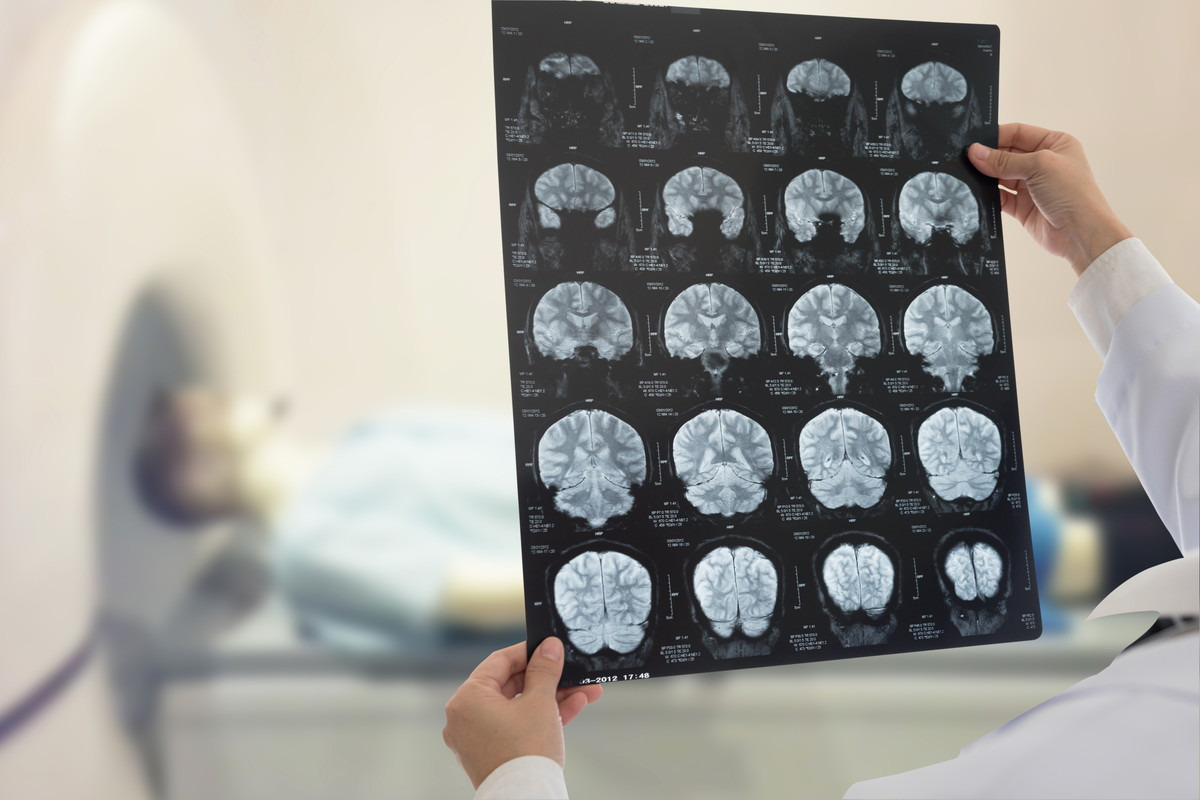

뇌 MRI 검사는 뇌혈관질환, 뇌종양, 뇌출혈, 신경학적 이상 증상 등을 평가할 때 필수적으로 활용되는 정밀 진단 장비이며, 강한 자기장을 이용해 인체 내부를 고해상도로 촬영하는 방식입니다. 최근 두통, 어지럼, 이상감각, 시야 흐림 등 다양한 증상에서 MRI 검사가 권고되는 사례가 증가하면서 많은 분들이 검사 비용, 촬영 시간, 조영제 여부에 따른 금식 필요성 등을 궁금해합니다.

뇌 MRI 검사는 크게 비용 구조와 촬영 절차, 금식 조건으로 나누어 이해할 수 있습니다. 비용은 건강보험 적용 여부가 가장 큰 변수이며, 시간은 MRI 장비 성능과 촬영 부위, 조영제 사용 여부에 따라 달라집니다. 금식은 기본적으로 필요 없지만 조영제 촬영에서는 일정 시간 금식이 요구된다는 특성이 있습니다.